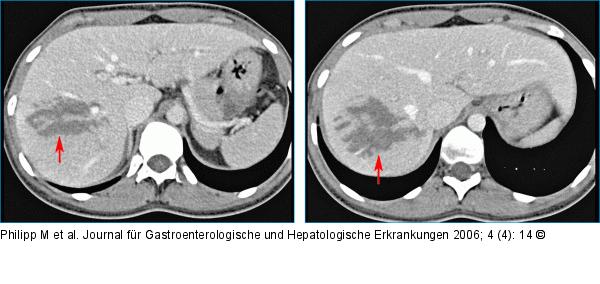

Abbildung 1a-b: Leberlappen - Ruptur Die axialen Multidetektor-CT-Bilder zeigten die Ruptur quer durch den rechten Leberlappen (Pfeile), jedoch keine freie Flüssigkeit im Abdomen. |

Die axialen Multidetektor-CT-Bilder zeigten die Ruptur quer durch den rechten Leberlappen (Pfeile), jedoch keine freie Flüssigkeit im Abdomen. |